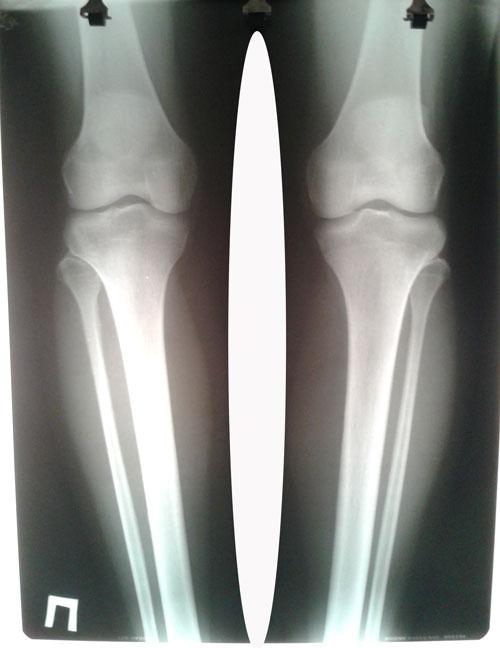

рентген до операции.

Вложения

20160709_125209.jpg